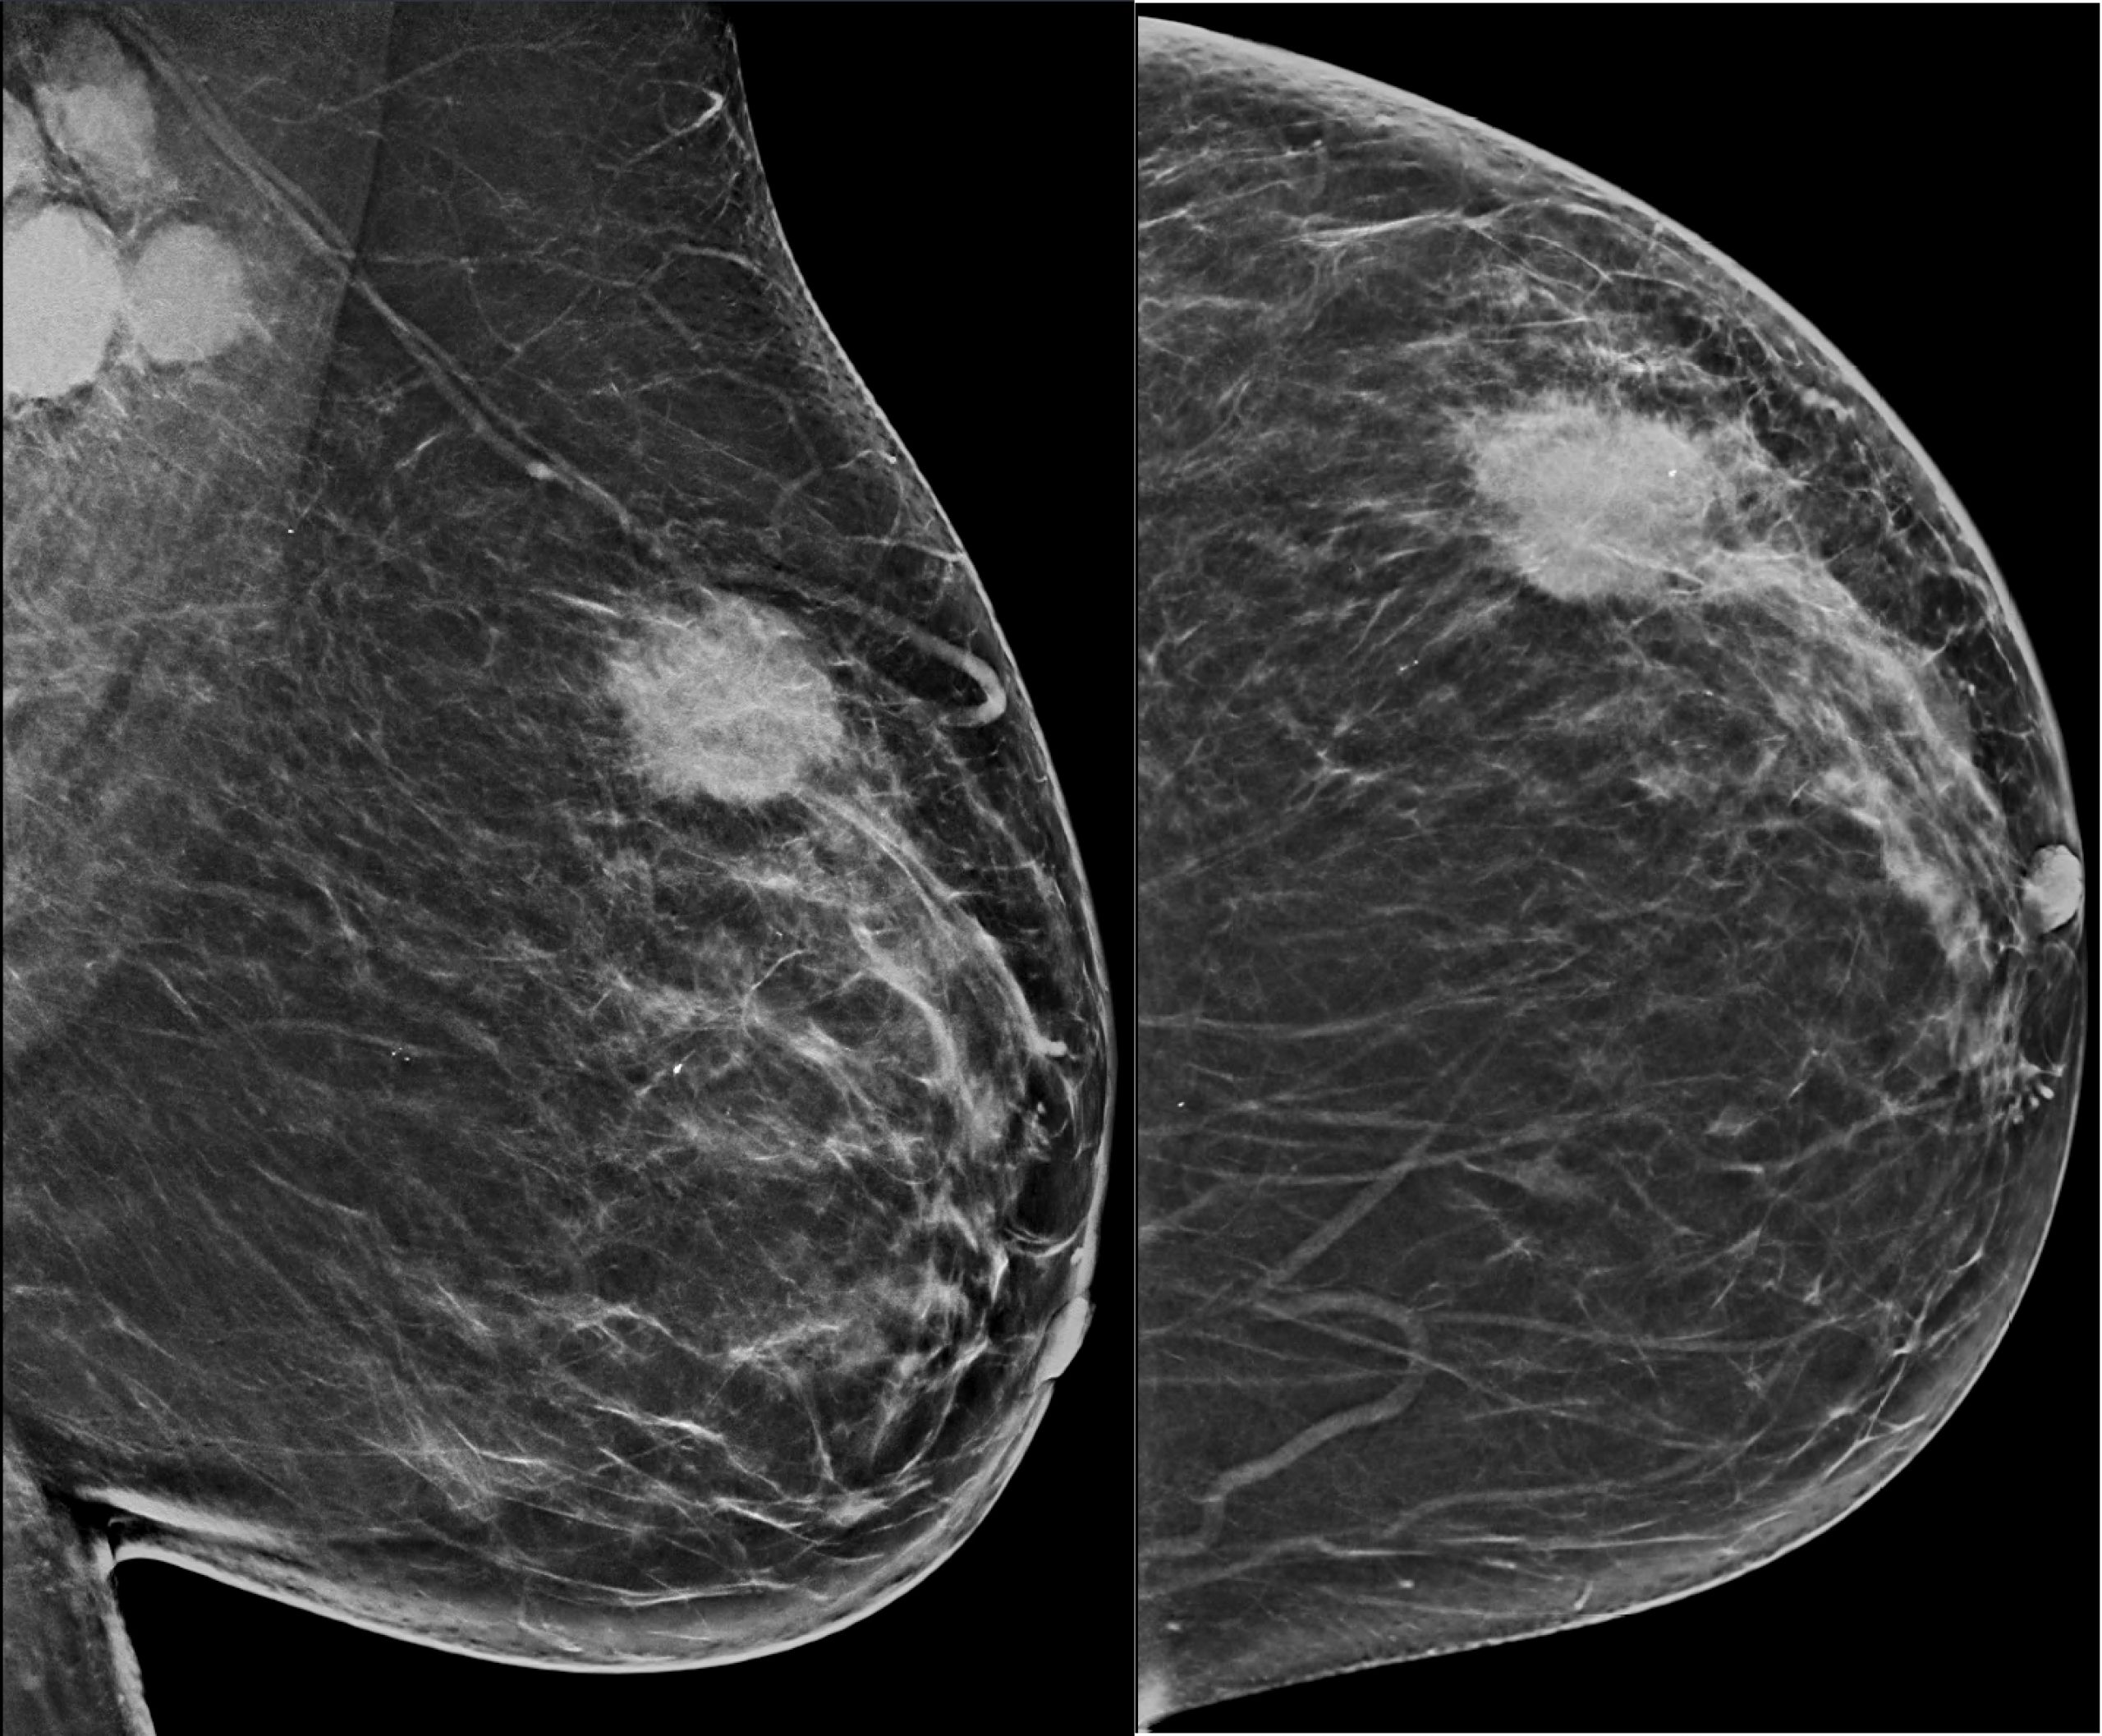

· Breast imaging is a type of medical technology that is used to identify or diagnose breast cancer in women. By giving radiological pictures of women's breasts, breast imaging medical technology aids in diagnosing many breast-related disorders. Nuclear imaging, mammography, breast ultrasonography, and magnetic resonance imaging (MRI) are the types of breast imaging technology. The main goal of this test is to detect breast cancer and other breast-related disorders at the earliest possible stage, when they are still treatable.

· Breast imaging is crucial for detecting breast cancer in its early stages. Several breast imaging modalities, however, use ionizing radiation for diagnosis. Ionizing radiation is used in digital mammography (DM) and digital breast tomosynthesis (DBT), as well as possible new breast screening techniques including contrast-enhanced mammography (CEM), whole-breast CT (WBCT), breast-specific gamma imaging (BSGI), molecular breast imaging (MBI), and positron emission mammography (PEM). Therefore, rising risk from radiation exposure will further challenge the breast imaging market.